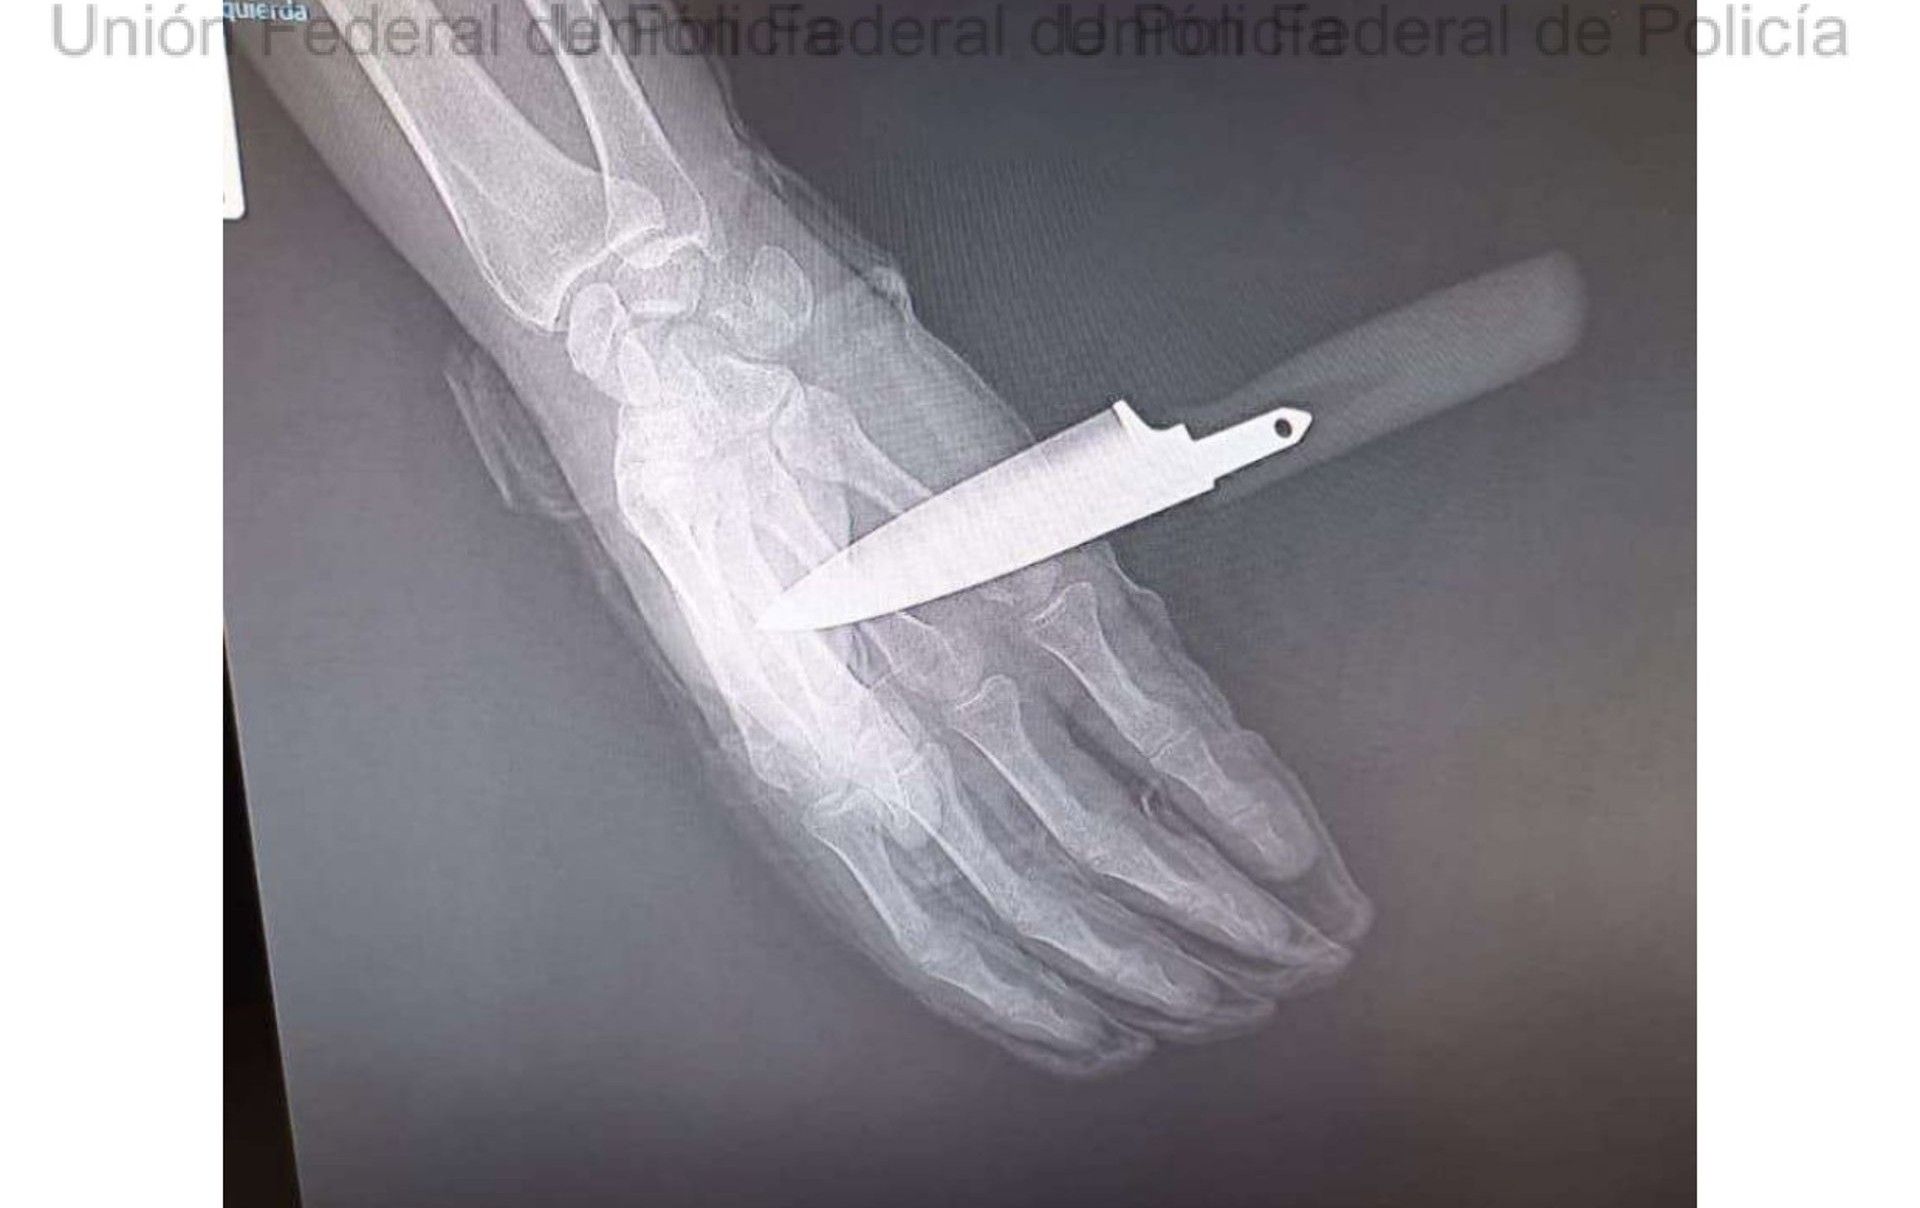

Uno de los detenidos está acusado de amenazar presuntamente a la menor con un arma blanca, además de realizarle tocamientos. Por ello se le atribuyen de forma provisional delitos de detención ilegal, amenazas graves, agresión sexual y contra la salud pública.